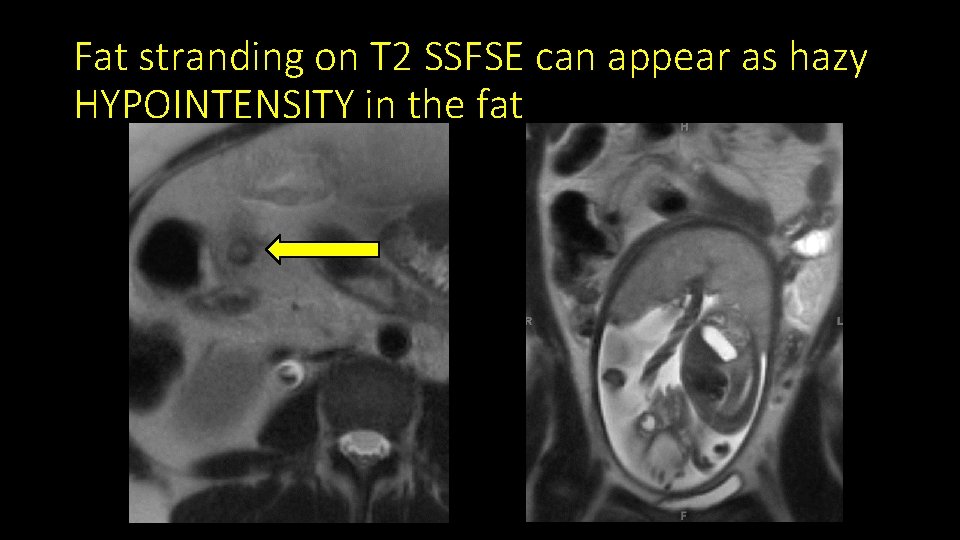

Fat stranding on T 2 SSFSE can appear as hazy HYPOINTENSITY in the fat